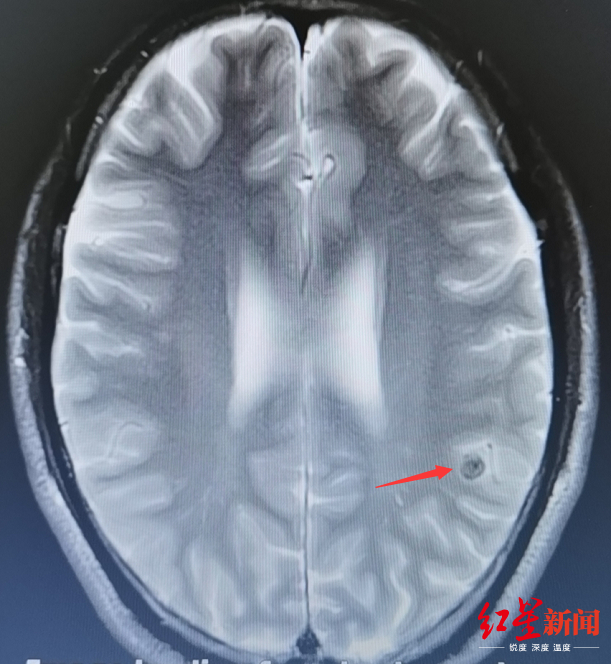

为了找出谭大哥疼痛的原因,医院神经内科执行主任何佳为他作了详细检查。拿到检查结果后,何佳发现,原来患者谭大哥脑内长了虫子!从各种影像检查资料来看,一个黑黑的小圆圈,中间有一个白点的小玩意就是这种虫子。进一步检查后证实,谭大哥感染的是一种繁殖能力极强的寄生虫,名为链状绦虫。这种虫的幼虫寄生于脑组织内,一般称为脑囊虫病。

据了解,感染了脑囊虫后,脑组织会受到损伤,病人会出现头疼、恶心、呕吐、肢体运动障碍、视物成双、视力下降、失明等症状,更有一部分病人会继发癫痫,最严重者甚至会危及生命。